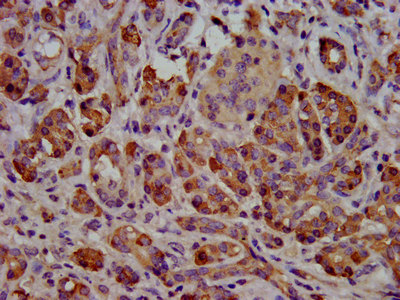

IHC image of CSB-PA325708LA01HU diluted at 1:500 and staining in paraffin-embedded human pancreatic tissue performed on a Leica BondTM system. After dewaxing and hydration, antigen retrieval was mediated by high pressure in a citrate buffer (pH 6.0). Section was blocked with 10% normal goat serum 30min at RT. Then primary antibody (1% BSA) was incubated at 4°C overnight. The primary is detected by a biotinylated secondary antibody and visualized using an HRP conjugated SP system.